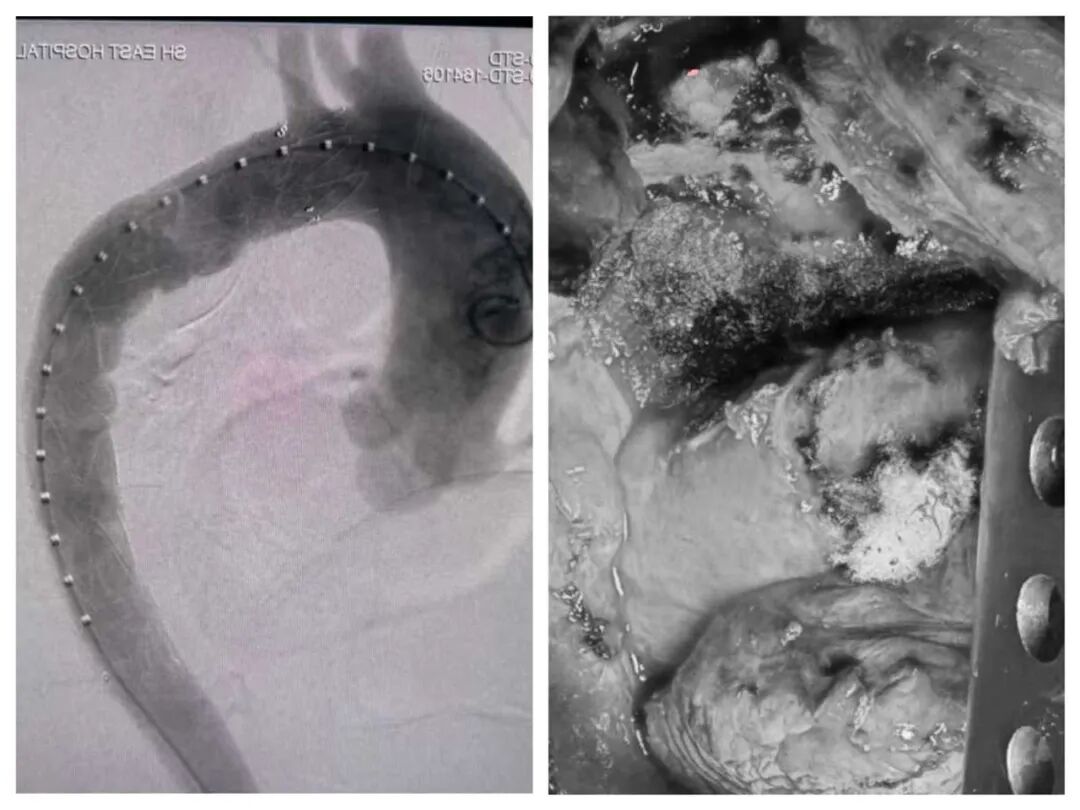

2. 血管“铠甲”先行:手术伊始,心外科主任刘俊、副主任施盛团队首先进行胸主动脉造影,并在主动脉弓及降主动脉被肿瘤包绕的关键部位精准植入覆膜支架,如同为血管穿上“铠甲”,有效隔绝了术中损伤大血管的风险。

3. 精细分离,步步为营:在血管保护到位后,方文涛主任主刀,带领团队迎难而上。凭借丰富的经验和娴熟的技术,耐心细致地分离胸腔致密粘连,逐步开辟安全通道。运用手术剪、超声刀、超声骨刀等精密器械,小心翼翼地剥离与血管神经紧密粘连的肿瘤组织。肿瘤周围密布易出血的“穿支”血管,每一步操作都力求毫米级的精准——既要彻底切除肿瘤,又要确保紧邻的大血管毫发无损,同时避免损伤致命神经。最终,这块巨大的“生命禁区”肿瘤被成功完整切除!